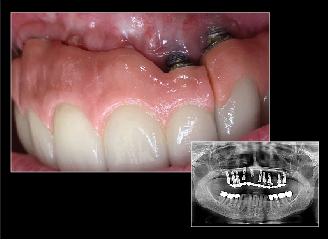

Fig 14. Specialist referrals can also be aided by clear photographs. In this case, an image captured using COCO Lux shows the exposure of implant threads and ulcerations under the prosthesis at 2 years.

Figure 14